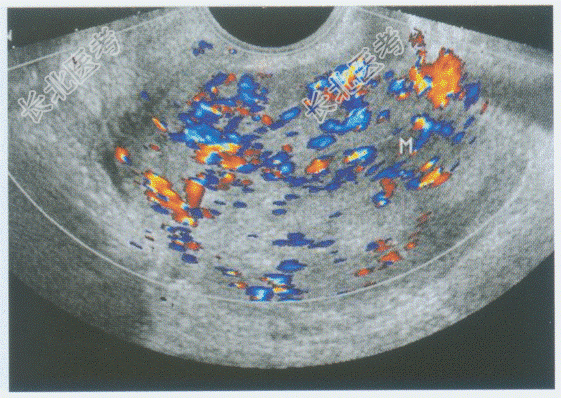

- 单项选择题临床资料:女性患者, 62岁,自述绝经10年, 阴道不规则出血半年。

超声综合描述:经阴道扫查子宫后位, 增大,子宫内膜不均匀性增厚, 与子宫肌层分界不清,侵及肌层深度>50%, 接近浆膜层,CDFI: 内可见丰富动、静脉血流信号,呈低阻型动脉频谱。见下图及彩图。

超声提示: A、子宫内膜腺瘤样增生

B、子宫内膜息肉

C、子宫内膜癌(侵及肌层>50%)

D、子宫肌瘤

E、子宫腺肌症